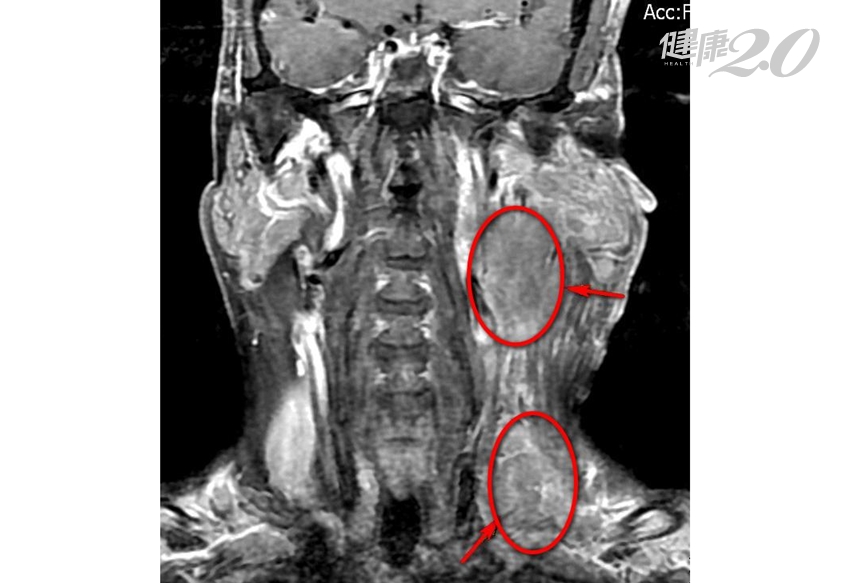

50歲的陳先生嚼食檳榔已有30年,今年初因為吞嚥困難就醫檢查,才發現罹患口咽癌,並轉移到淋巴腺,最大的淋巴結接近9公分。幸好,陳先生不僅接受化療及放射治療,還徹底戒除了嚼食檳榔的習慣,幾個月後腫瘤成功縮小到在影像檢查上看不到的狀態。

▲電腦斷層掃描顯示陳先生的口咽腫瘤位置(紅圈處)。